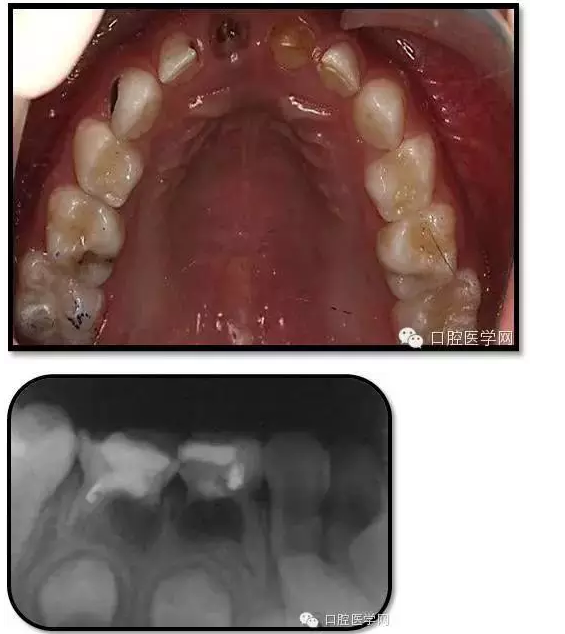

85O、84DO充填完好,邊緣密合,叩(-),不松,齦無紅腫。X線:84、85根分歧透射影,44、45骨硬板連續(xù),恒牙胚上方骨板厚約2-3mm。75帶環(huán)絲圈式間隙保持器完好,無松動,無咬合不適。64MO中齲。 64MO中齲去腐凈,自酸蝕,SEBOND,樹脂充填。 口腔衛(wèi)生宣教,囑3個月后復(fù)診。

1、根分歧處病變姑息保留牙的治療及轉(zhuǎn)歸。 75牙體缺損過大,根分岐大面積透射影并累及根尖周。故拔除后間隙保持。84、85初診時已做過根管治療,有繼發(fā)齲,牙根吸收較多,可見大面積的根分歧病變,但根尖無病變,考慮44、45表面骨硬板連續(xù),故只對患牙進(jìn)行了繼發(fā)齲充填治療,姑息保留。3個月復(fù)查時,85O、84DO充填完好,邊緣密合,叩(-),不松,齦無紅腫。7個月復(fù)查時85O、84DO充填完好,邊緣密合,叩(-),不松,齦無紅腫。X線:84、85根分歧透射影,44、45骨硬板連續(xù)。 回顧整個治療過程,應(yīng)定期復(fù)查84、85姑息保留牙,且間隔時間不宜過長。觀察根分歧病變的恢復(fù)情況,一旦發(fā)現(xiàn)恒牙胚受累及,則需采取積極措施。